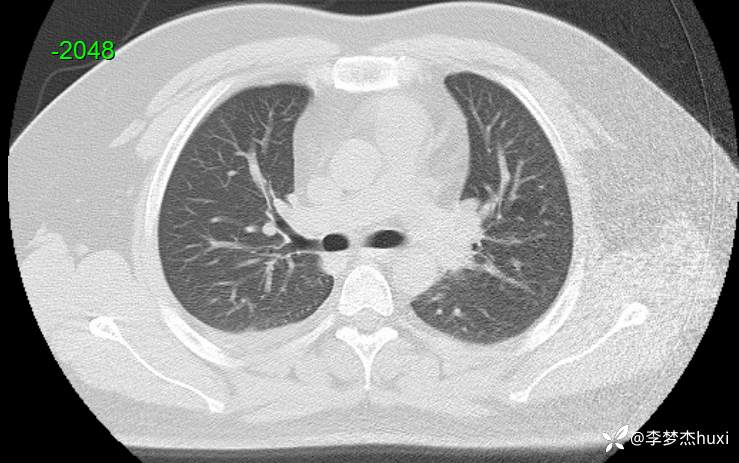

【现病史及既往史】: 1.患者青年 男,患者缘于2天前无诱因出现胸痛,为前胸痛,伴后背疼痛,咳嗽及深呼吸时明显,伴咳嗽,痰不易咳出,伴恶心、呕吐,伴发热,体温最高达37.7℃,无寒战,无咯血,院外未应用药物治疗,症状无明显好转,为求进一步治疗来院就诊,门诊查胸部CT提示:双肺炎症,较前进展,双肺纹理增重,右肺实性结节,建议随诊复查,双侧胸膜局部增厚,右侧胸腔少量积液。以“肺炎”收住院;。

【检查】: 4.辅助检查:心电图示:窦性心动过速,门诊查胸部CT提示:双肺炎症,较前进展,双肺纹理增重,右肺实性结节,建议随诊复查,双侧胸膜局部增厚,右侧胸腔少量积液。